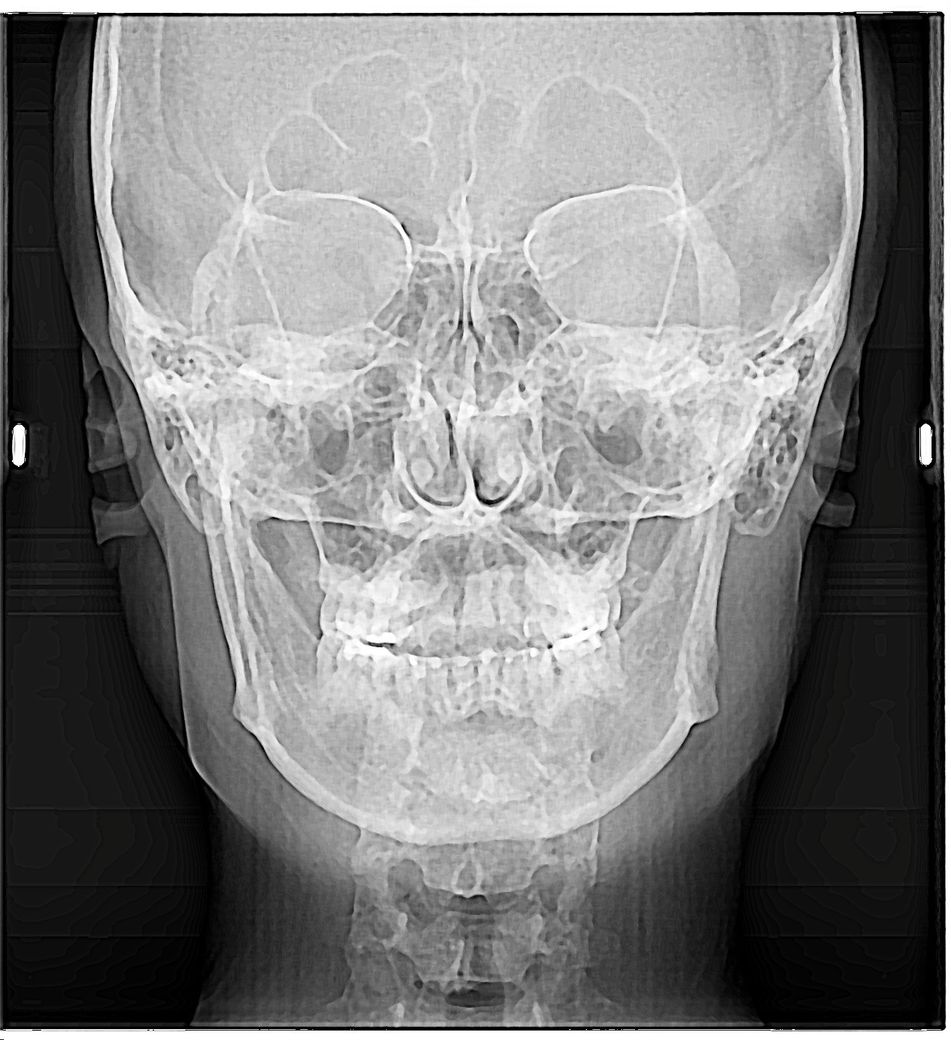

치아교정 어금니 높이 맞추면 안면비대칭 개선될까요?

(이건 제 X-ray)

턱이 왼쪽으로 휜게 부정교합이라서 인가요? 아니면 턱이 비대칭으로 왼쪽으로 휘어있어서 어쩔 수 없이 치아들교합도 저런건가요? 뭐가 먼저 문제인지 모르겠어서요.

치아교정으로 미니스크류로 오른쪽 윗 어금니들 정출된거 위로 올리고 바깥으로 넓히고, 왼쪽 위 어금니 내리면요. 턱관절+턱 비대칭+ 입술비대칭 개선될까요?? 아님 턱+입술 비대칭은 그냥 그대로인가요??

치열로 인해서 구강안모가 비대칭이라면 교정을 하면 어느정도 해결은 되겟지만 골격적으로 문제가 잇다면 양악과 교정을 병행하셔야될수도 있습니다.

치열로 인해서 생긴 비대칭이라면 교정을 하게 되면 비대칭이 해결될 수 있습니다. 하지만 공격적인 비대칭이라면 교정을 해도 원인이 해결되지 않을 수 있습니다. 골격적인 비대칭이라면 수술을 동반한 교정 치료가 필요할 수 있습니다.